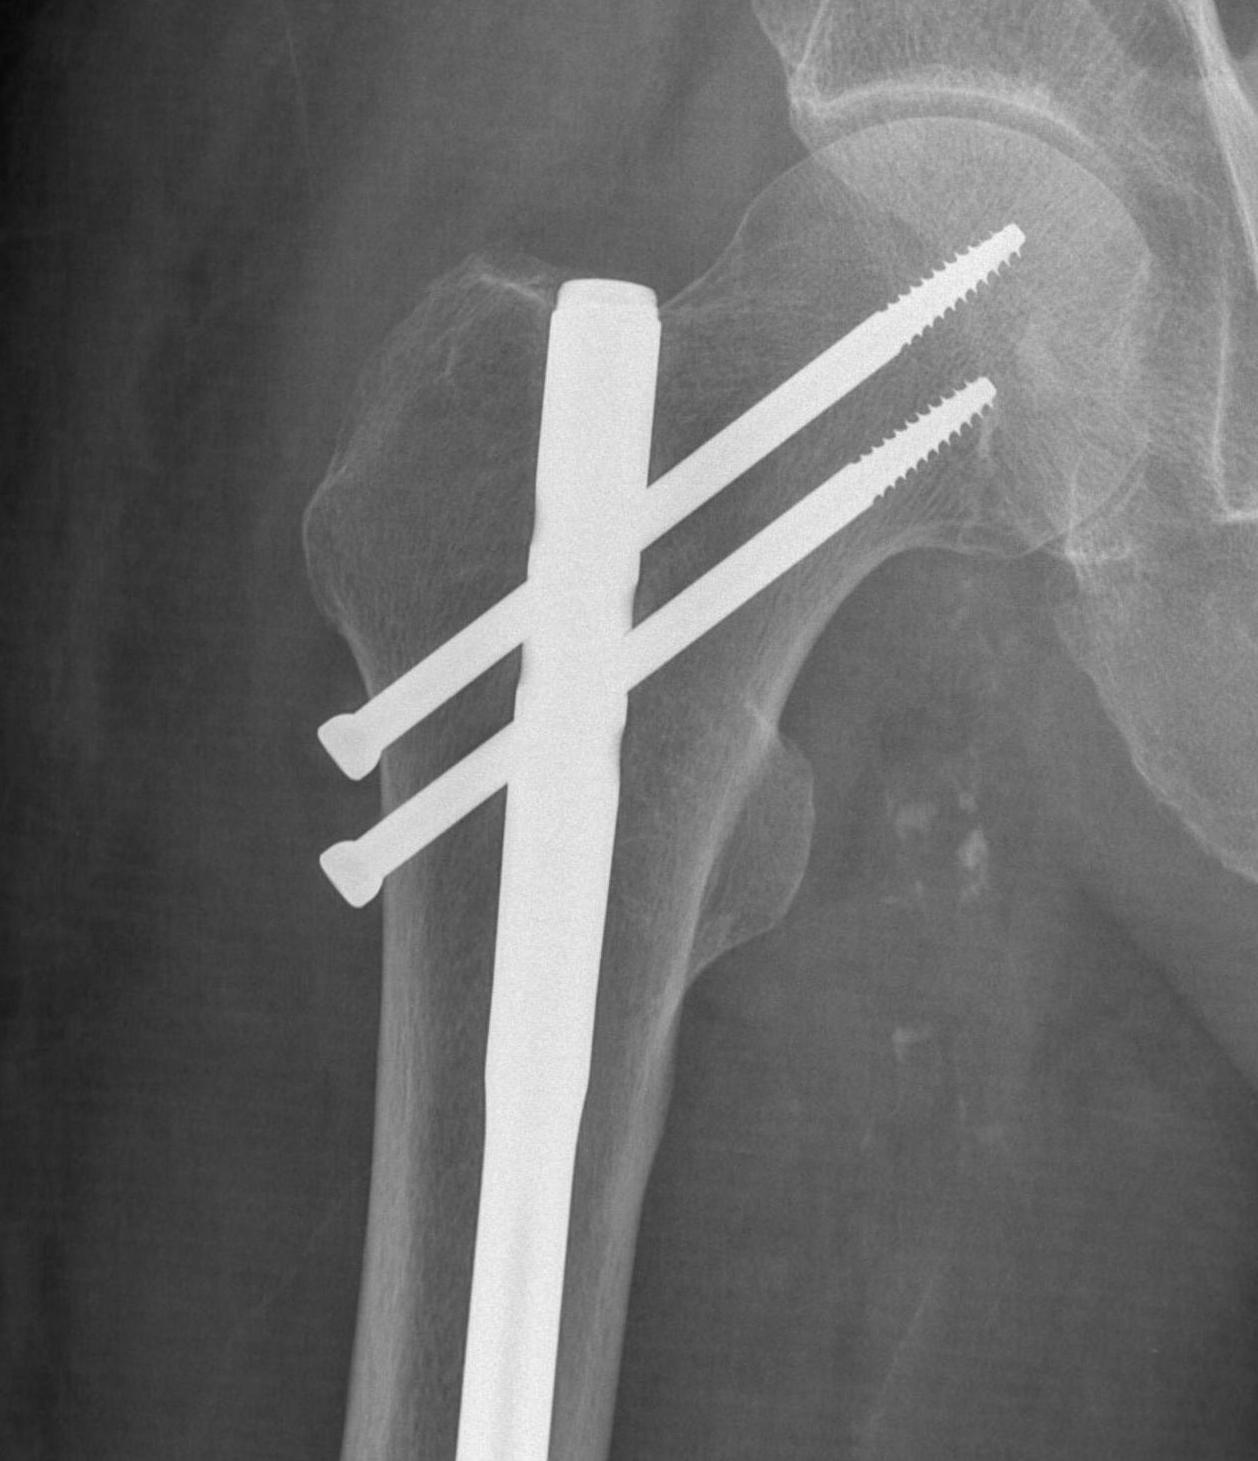

B. Cephalomedullary nails

- gold standard

Piriformis reconstruction Gamma nail TFNA with helical screw Intertan nail

Entry point

Greater trochanteric

- simple

- need proximal fragment reduced

Piriformis

- may aid reduction, as a trochanteric nail will push proximal fragment into valgus

- more difficult to obtain